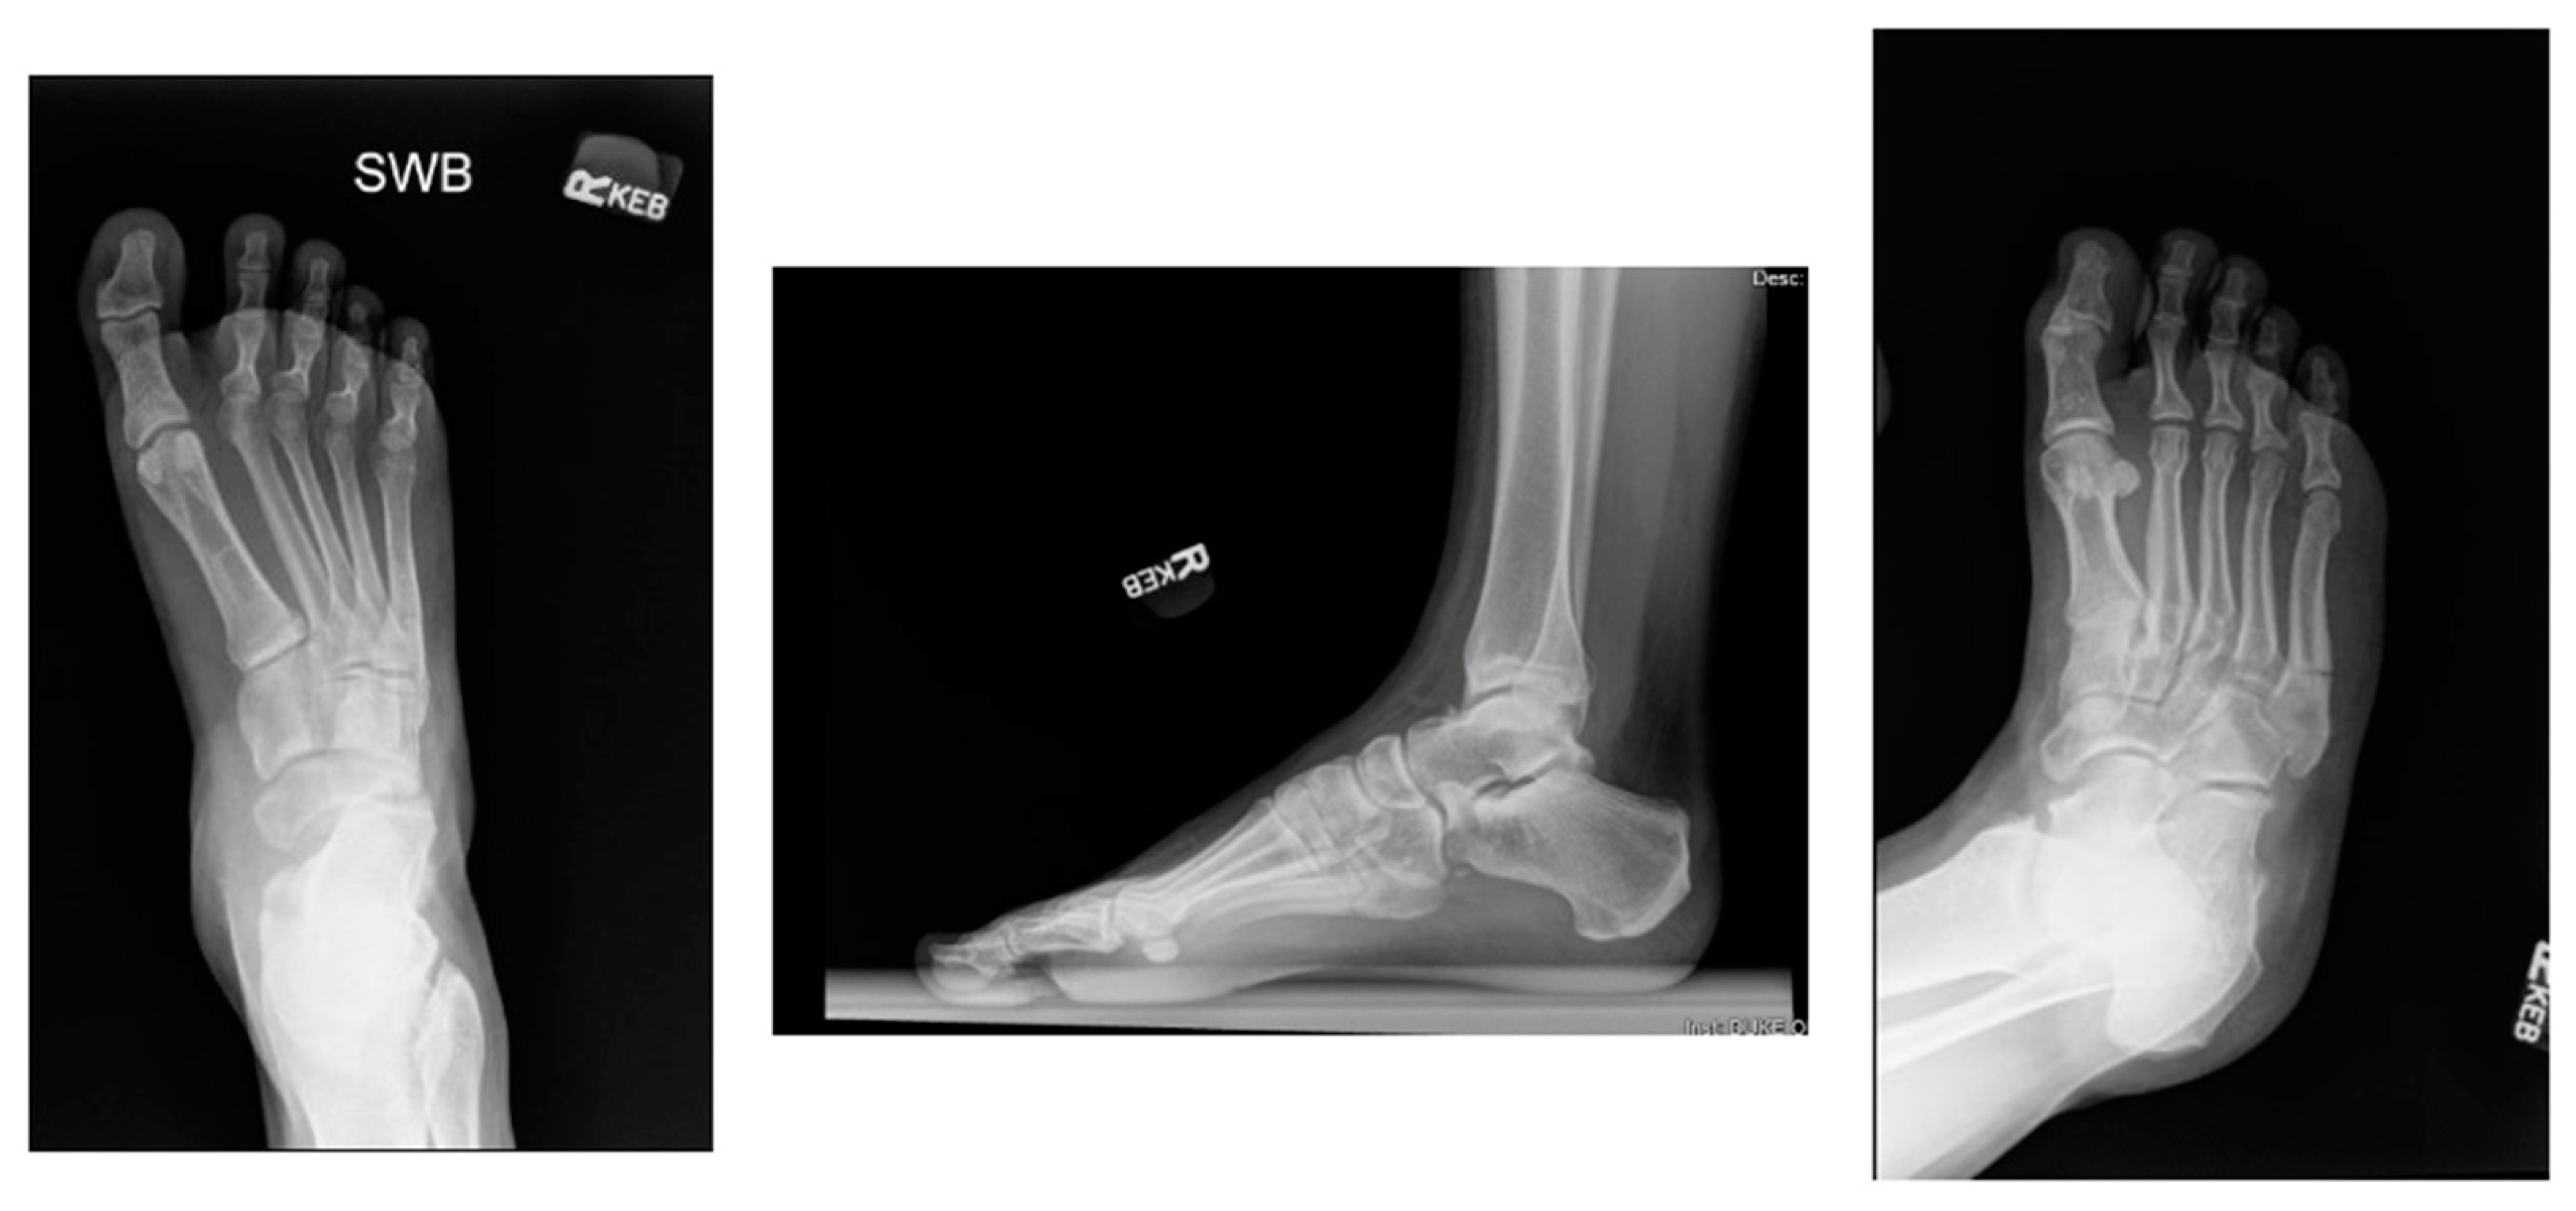

3.2. Diagnosis

- Metzl, J.A.; Bowers, M.W.; Anderson, R.B. Fifth Metatarsal Jones Fractures: Diagnosis and Treatment. JAAOS-J. Am. Acad. Orthop. Surg. 2022, 30, e470–e479. [Google Scholar] [CrossRef] [PubMed]

- Riegger, M.; Muller, J.; Giampietro, A.; Saporito, A.; Filardo, G.; Treglia, G.; Guidi, M.; Candrian, C. Forefoot Adduction, Hindfoot Varus or Pes Cavus: Risk Factors for Fifth Metatarsal Fractures and Jones Fractures? A Systematic Review and Meta-Analysis. J. Foot Ankle Surg. 2022, 61, 641–647. [Google Scholar] [CrossRef] [PubMed]

- Raikin, S.M.; Slenker, N.; Ratigan, B. The association of a varus hindfoot and fracture of the fifth metatarsal metaphyseal-diaphyseal junction: The Jones fracture. Am. J. Sports Med. 2008, 36, 1367–1372. [Google Scholar] [CrossRef]

- Fleischer, A.E.; Stack, R.; Klein, E.E.; Baker, J.R.; Weil, L., Jr.; Weil, L.S., Sr. Forefoot Adduction Is a Risk Factor for Jones Fracture. J. Foot Ankle Surg. 2017, 56, 917–921. [Google Scholar] [CrossRef] [PubMed]